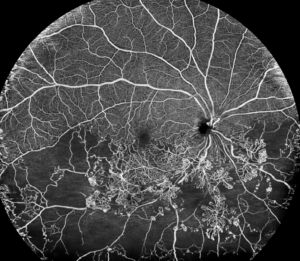

O diagnóstico é feito através do mapeamento da retina (fundo de olho) e da tomografia da retina (OCT).

Tomografia da retina (OCT) evidenciando o buraco de mácula

Tomografia de retina pré e pós a cirurgia, com recuperação da anatomia normal da retina.